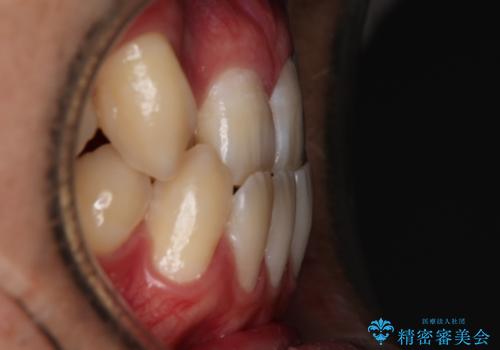

左右の噛み合わせが反対咬合であることと下顎の皮質骨が薄いため治療計画をしっかりと立てて行う必要のあるケースでした。

その点を考慮して、リンガルアーチを用いて奥歯を遠心移動し、前歯にIPR(歯と歯の間を削る処置)を行うことでスペースを作って歯並びを整えていく計画を立てました。

リンガルアーチを用いて奥歯を遠心移動し、前歯にIPR(歯と歯の間を削る処置)を行うことでスペースを作って歯並びを整えていく計画を立てました。

心配していた歯肉退縮も起こらず、前歯の噛み合わせと歯並びが綺麗に改善されました。